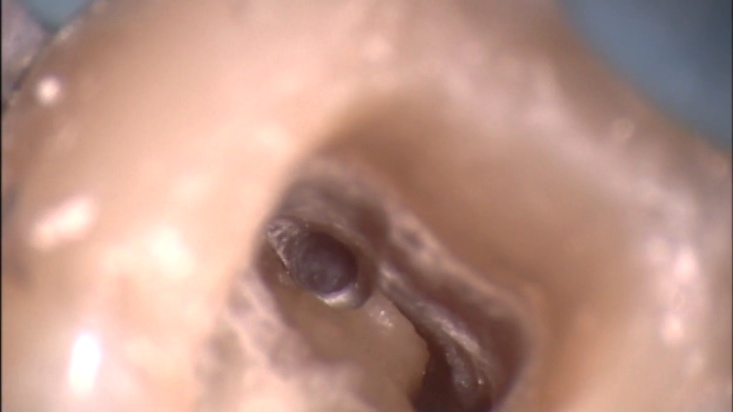

Сл. 37.99

Сл. 37.99 а) Предоперативна радиографија на долниот десен втор молар открива присуство на стапалки во каналите на мезијалниот корен. б) Фотографијата на 15x ја покажува локацијата на стапалките (на надворешните ѕидови на коренските канали) и оригиналните канали. в) Интраоперативниот филм открива дека стапалката е заобиколен. г) Сместен конус. д) Постоперативен филм.